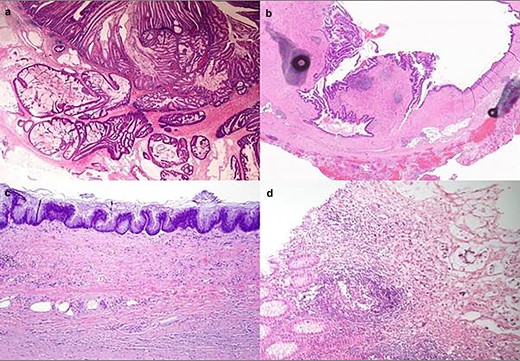

Nice summary on management of appendix tumours by our senior fellows @TheChristieNHS #cpoc Chris Kearsey and @nige_day free in this months @BJSurgery @BjsOpen @BJSAcademy @young_bjs

@BJSurgery

BJS

4 years

Free to access in July's BJS: ‘It’s not just a mucocoele’—pathology and treatment of appendix tumours https://t.co/qMKJ0OfOpT @AmyLightnerMD @bplwijn @des_winter @ksoreide @MalinASund @evanscolorectal @nfmkok @robhinchliffe1 @young_bjs